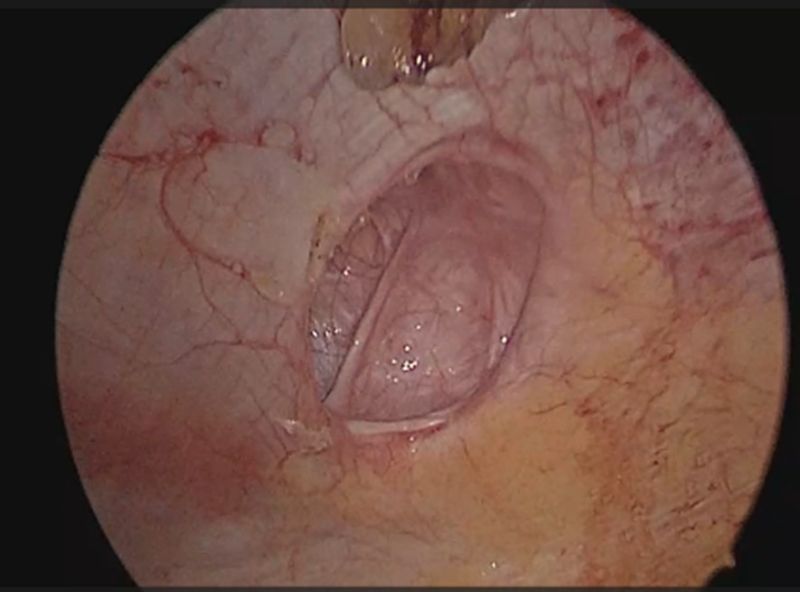

Plain CT scan of the abdomen was done that revealed a 3.1 cm sized defect in the anterior abdominal wall along the left lateral lumbar region with omentum and bowel loops as hernial contents. A diagnosis of trocar site incisional hernia (TSIH) was made, and the patient was planned for laparoscopic IPOM for the left lumbar hernia. Patient was placed in the supine position with a slight right tilt arms tucked by the side. Pneumoperitoneum was created using a Veress needle at the palmer’s point. Optical view entry using a 5mm optical trocar was done at the right hypochondrium, then a right iliac 5mm port and another 10mm port in the right lumbar region were placed under vision for instrumentation (figure 1). Adhesions were visualized over the previous mesh and adhesiolysis was performed. A defect in left lumbar region was seen, and it was approximated using absorbable barbed sutures in a continuous fashion. A 15x15 composite mesh was placed over the defect with a margin of 5 cm on either side. The defect was seen to be overlying on the previous mesh. Mesh was sutured using absorbable barbed sutures and inner crowning of the mesh was done using absorbable tacks. TAP block was given laparoscopically and proper haemostasis was achieved. 10mm port site was closed using a non-absorbable figure-of-8 stitch. Patient was shifted to ward, and she was managed with intravenous analgesics, antibiotics as well as antacids. Visual analogue scale (VAS) score for pain on post-operative day-1 was 3 out of 10. The patient recovered well after the procedure and was discharged in a hemodynamically stable state on post-operative day 2.

Figure 3: Defect in the left lumbar region